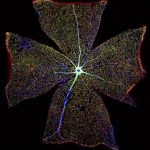

Surface of a Mouse Retina

The retina, located at the back of the eye, contains light-sensitive cells responsible for converting light into electrical nerve signals that the brain can process. As a result of aging or injury the retina can lose this function, causing vision loss. This image was created by digitally stitching together over 400 images to form one large image, so as to show the entire surface of a mouse retina. Blood vessels (blue) can be seen radiating from the centre of the image, supplying the entire retinal surface. Astrocytes, specialist cells of the nervous system, are double stained in red and green. These cells perform many functions – including maintaining and delivering nutrients to the nerves and the brain, and supporting the repair processes of the brain and spinal cord following injury – and are important for nerve survival and regeneration. Here, scientists are researching whether the function of astrocytes changes during retinal degeneration, which may lead to the development of new treatments for vision loss.

GABRIEL LUNA, NEUROSCIENCE RESEARCH INSTITUTE, UNIVERSITY OF CALIFORNIA, SANTA BARBARA